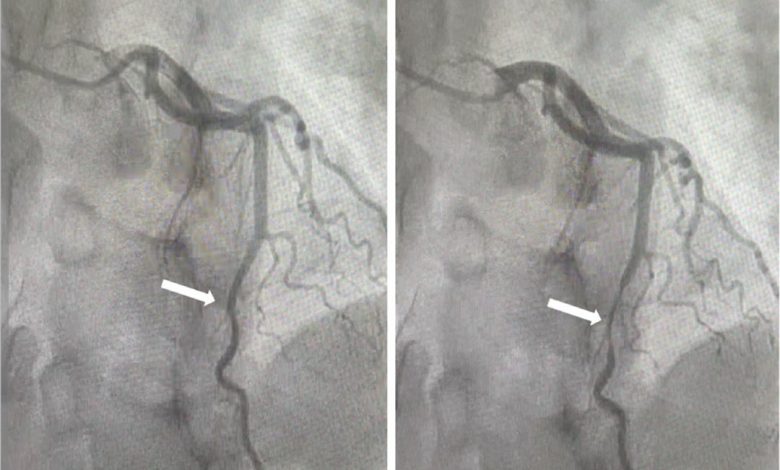

أوضح استشاري أمراض القلب، الدكتور خالد النمر، أن ما يُعرف بـ “جسر القلب” هو حالة يكون فيها جزء من عضلة القلب يغطي أحد الشرايين التاجية، وغالبًا الشريان الأمامي، مشيرًا إلى أن هذه الظاهرة تظهر لدى نحو 20% من الأشخاص عند إجراء الأشعة المقطعية.

وأكد أن السبب الرئيسي الذي يجب البحث عنه عند ألم الصدر هو وجود تكلسات أو تضيق حقيقي في الشرايين، بينما لا يُعتد بـ “جسر القلب” كسبب إلا إذا ثبت تأثيره الوظيفي عبر فحوصات دقيقة مثل التصوير النووي للقلب أو القياسات الداخلية المتقدمة مثل IVUS أو FFR، مشددًا على أن الحالة شائعة لكنها غالبًا ليست مصدر المشكلة الصحية.